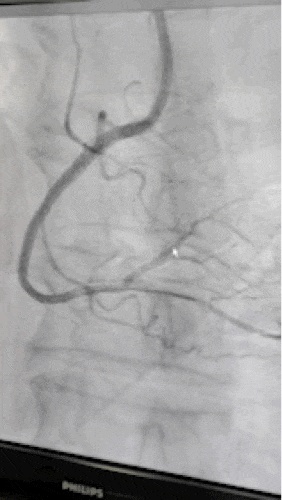

入院后,安排该患者完善相关检查,提示目前患者血管病变严重,左前降支近段狭窄70%-80%、粗大对角支近端90%狭窄,左回旋支中远段支架内完全闭塞,前向血流TIMI  0级,可见少量侧枝逆向血流,右冠状动脉中近段完全闭塞,前向血流TIMI  0级,可见同侧少量侧枝循环逆向血流。

9年前右冠脉为慢性闭塞病变,目前依然是CTO病变,但有少量自身侧枝循环,病变较前更加复杂了。

9年前在回旋支植入的2枚支架

目前支架内完全闭塞